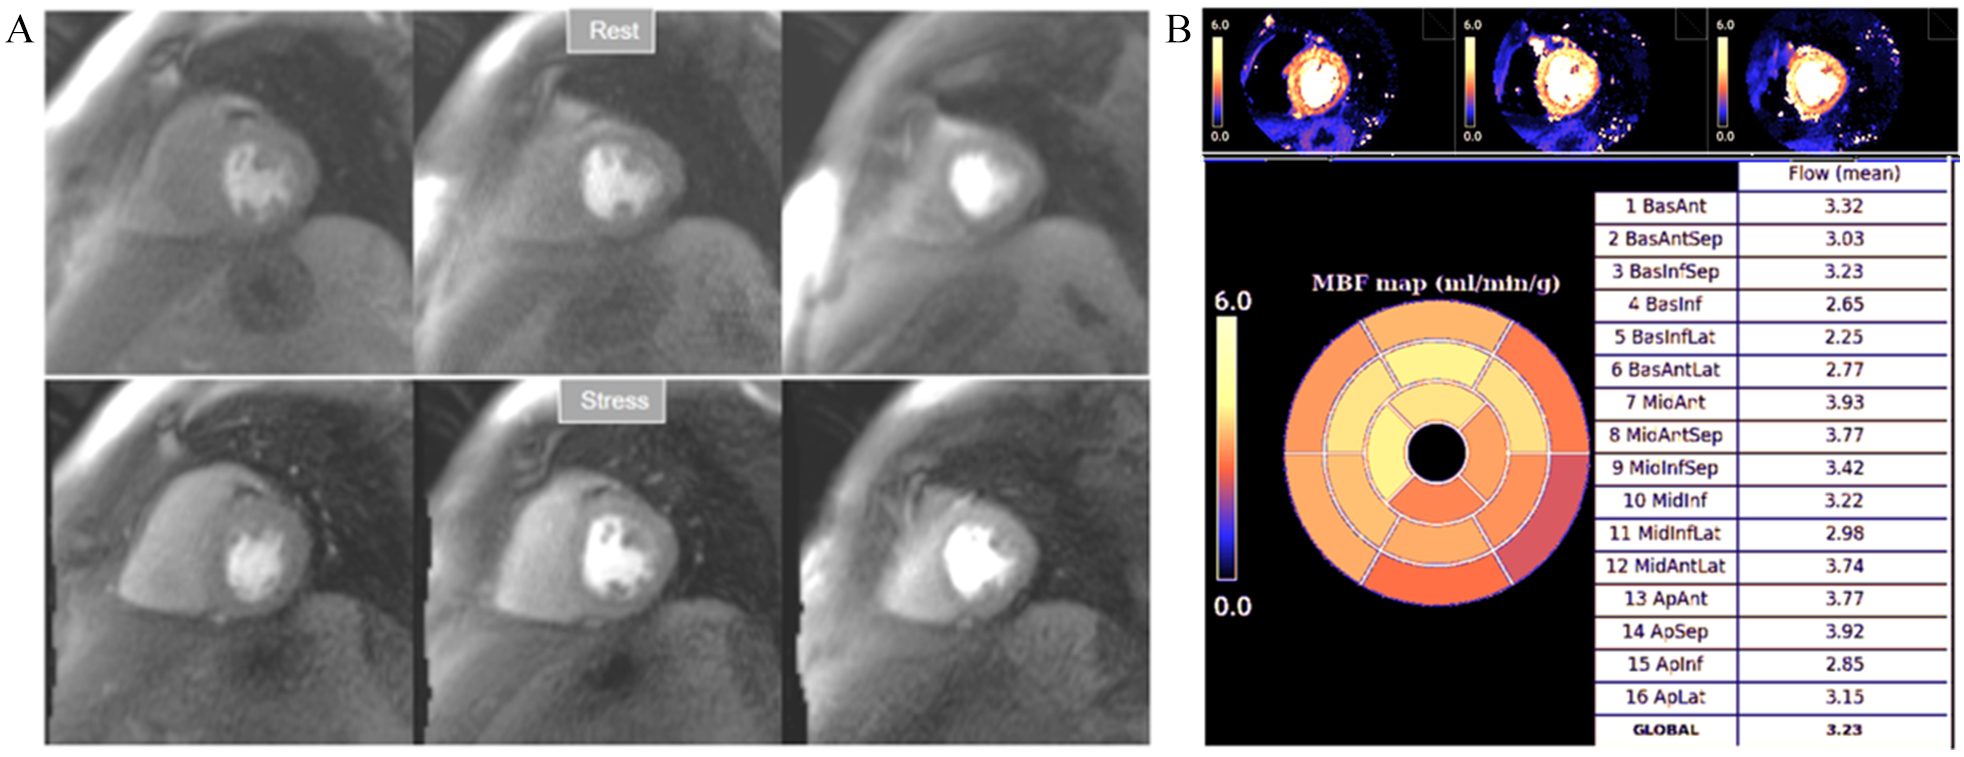

MVD is another entity where the contribution of perfusion mapping has been essential, as the disorder is frequently overlooked due to the lack of appropriate, non-invasive, reliable tests for its assessment. While patients with MVD present with subendocardial hypoperfusion [41], a circumferential defective enhancement at first pass is detected at visual analysis of perfusion CMR only in a proportion of them (Fig. 9). A first study using QP CMR on patients with angina and no obstructive CAD showed that stress MBF and MPR were significantly reduced with respect to a control group of normal individuals [86]. A further study comparing QP CMR with invasive measurements of CFR confirmed these findings [87] establishing as optimal thresholds for the diagnosis a global MPR of 2.19 and, particularly, a subendocardial global MPR of 2.41. Interestingly, only 58% of patients with proven MVD presented with visually detectable defects in this study.